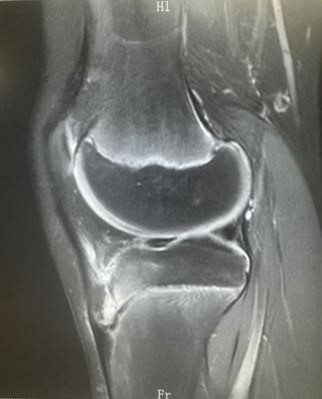

2、MRI:(早期)胫骨结节、髌韧带水肿、髌下囊渗出性病变、无明显骨质形态改变;(进展期)二次骨化中心部分软骨撕脱;(终末期)可见游离碎骨片影;(愈合期)胫骨结节骨性愈合、无明显游离骨片。